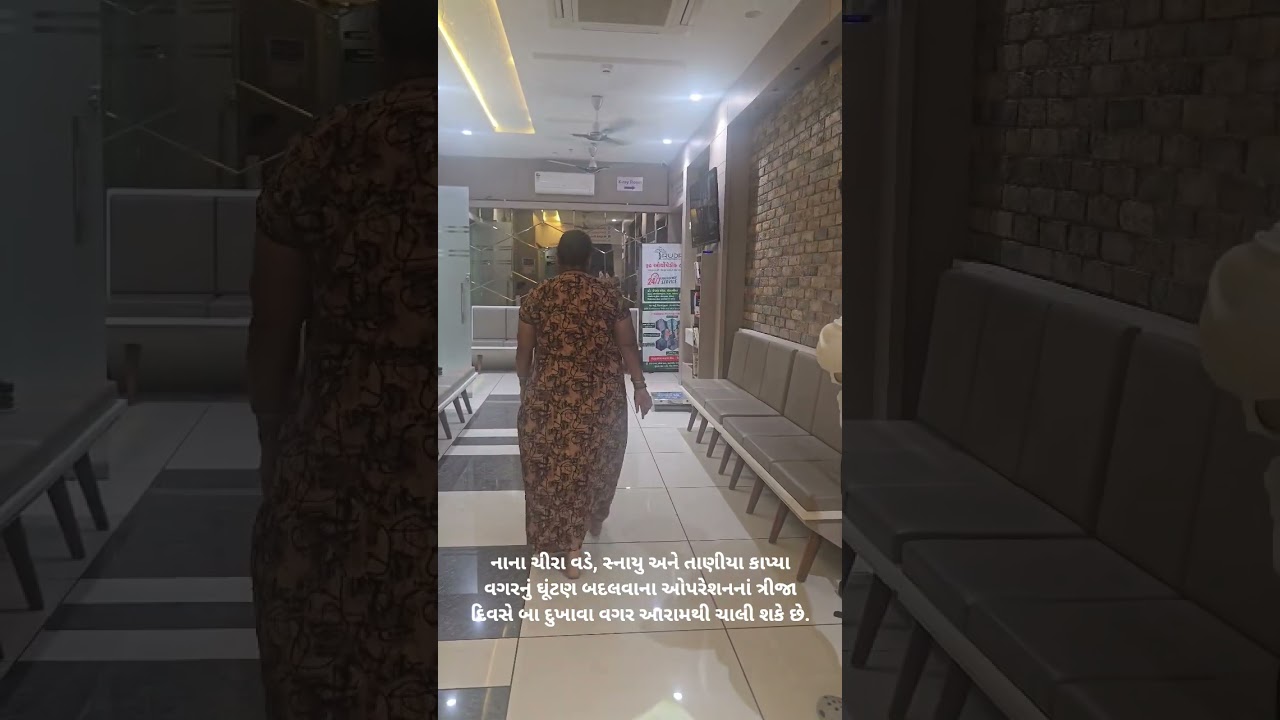

We specialize in Joint Replacement Surgery in Surat, including Knee Replacement, Hip Replacement, and Revision Joint Replacement procedures with modern surgical techniques and personalized patient care.

Dr. Italiya has extensive expertise in trauma care, joint replacement surgeries (knee & hip), fracture management, arthritis treatment, and spine-related conditions. His approach focuses on long-term recovery and functional restoration rather than temporary pain relief.

Personalized physiotherapy programs for post-surgery recovery, sports injuries, arthritis, and chronic pain management.